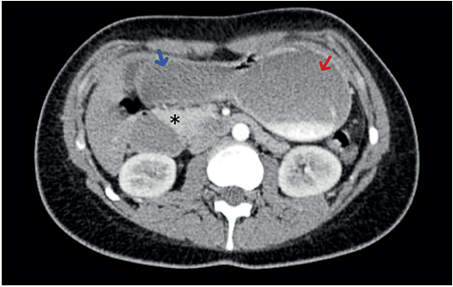

Presentamos el caso de una paciente de 22 años de edad, con antecedente de trastorno límite de la personalidad, consultante en múltiples ocasiones al servicio de urgencias por náuseas y episodios eméticos persistentes, asociados a dolor y distensión abdominal. La tomografía computarizada (TC) de abdomen con contraste evidenció disminución del ángulo y la distancia entre la aorta y la arteria mesentérica superior, confirmando el diagnóstico de síndrome de Wilkie (Figura 2), por lo que se inició manejo médico, pero fue fallido.